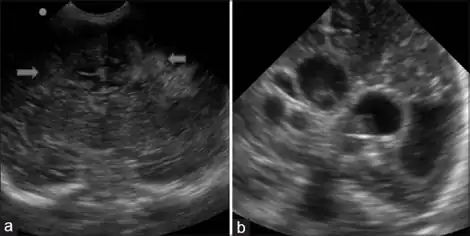

As previously noted, there are often few signs of white matter injury in newborns. Occasionally, physicians can make the initial observations of extreme stiffness or poor ability to suckle. The preliminary diagnosis of PVL is often made using imaging technologies. In most hospitals, premature infants are examined with ultrasound soon after birth to check for brain damage. Severe white matter injury can be seen with a head ultrasound; however, the low sensitivity of this technology allows for some white matter damage to be missed. Magnetic resonance imaging (MRI) is much more effective at identifying PVL, but it is unusual for preterm infants to receive an MRI unless they have had a particularly difficult course of development (including repeated or severe infection, or known hypoxic events during or immediately after birth).[5] No agencies or regulatory bodies have established protocols or guidelines for screening of at-risk populations, so each hospital or doctor generally makes decisions regarding which patients should be screened with a more sensitive MRI instead of the basic head ultrasound.

PVL is overdiagnosed by neuroimaging studies and the other white matter lesions of the brain are underestimated. It is important to differentiate PVL from the following major white matter lesions in the cerebral hemispheres: edematous hemorrhagic leukoencephalopathy (OGL), telentsefalny gliosis (TG), diffuse leukomalacia (DFL), subcortical leukomalacia (SL), periventricular hemorrhagic infarction (PHI), intracerebral hemorrhage ( ICH), multicystic encephalomalacia (ME), subendymal pseudocyst. Diffuse white matter lesions of the cerebral hemispheres of the brain, accompanied by softening and spreading to the central and subcortical areas are more likely DFL, PHI and ME.[1]